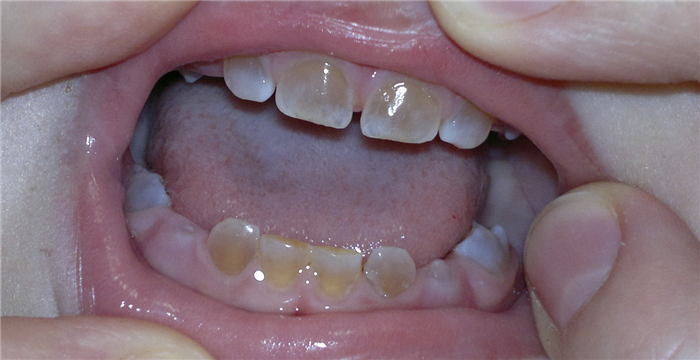

При клиническом обследовании мальчика 1,9 года выяснилось, что ребенок родился в срок, доношенный. Вскармливание грудное до 2 месяцев, прикорм с 5 месяцев, в 1,2 года перешел на общий стол. С 1 месяца принимал «Аква Д3» до года, с года — «СаКомпливит» детский. До года переболел ОРВИ три раза. В 1,6 месяца перенес пневмонию. Первый зуб появился в 7,5 месяца. К году прорезалось 6 зубов. После прорезывания зубы были полупрозрачные, серого цвета, режущие бугорки невыраженны (рис. 5).

Рис. 5. Вид молочных зубов у мальчика.

Со временем цвет зубов изменился до янтарного. В год и семь месяцев зуб 51 скололся в пределах эмали. На данный момент не прорезались только 55, 65 зубы.